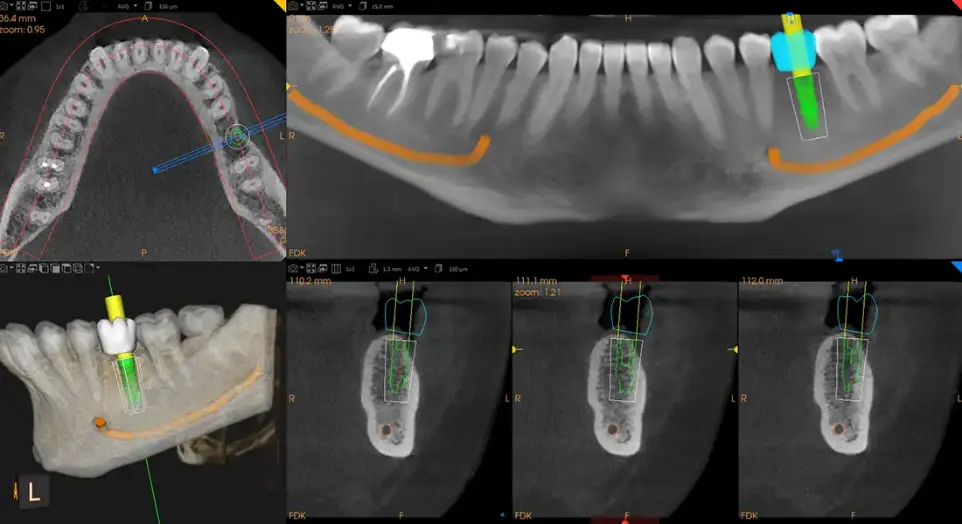

Discover the versatility of the CS 8200 3D, showing dynamic views of nerves, bone density, root structures, and airway pathways. This video demonstrates how its powerful 3D scans improve treatment accuracy even in the most complex cases.

Each scan provides precise data for implants, root canals, TMJ therapy, or orthodontics, ensuring accuracy and comfort from day one.

Dental Implants: Exact placement for lasting success.

At our practice, we focus on technologically supported care, not just aesthetics. Using the CS 8200 3D system, we can:

• Diagnose issues hidden from your usual exam and X-rays

• Plan treatments (implants, root canals, orthodontics) with more precision

• Minimize radiation exposure while improving image clarity

• Perform more in-house work, reducing referral delays